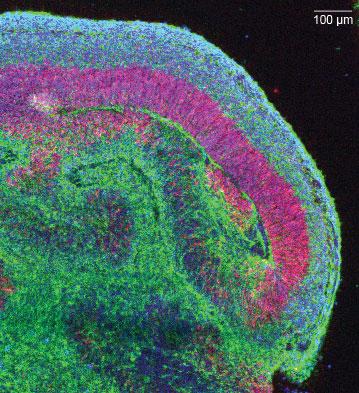

Срез одного «долькового» участка кортикальной ткани внутри органоида (нейроны

Срез одного «долькового» участка кортикальной ткани внутри органоида (нейроны — зелёным, нервные стволовые клетки — красным, все ядра клеток окрашены в синий). Фото: Мэделин Ланкастер / IMBA